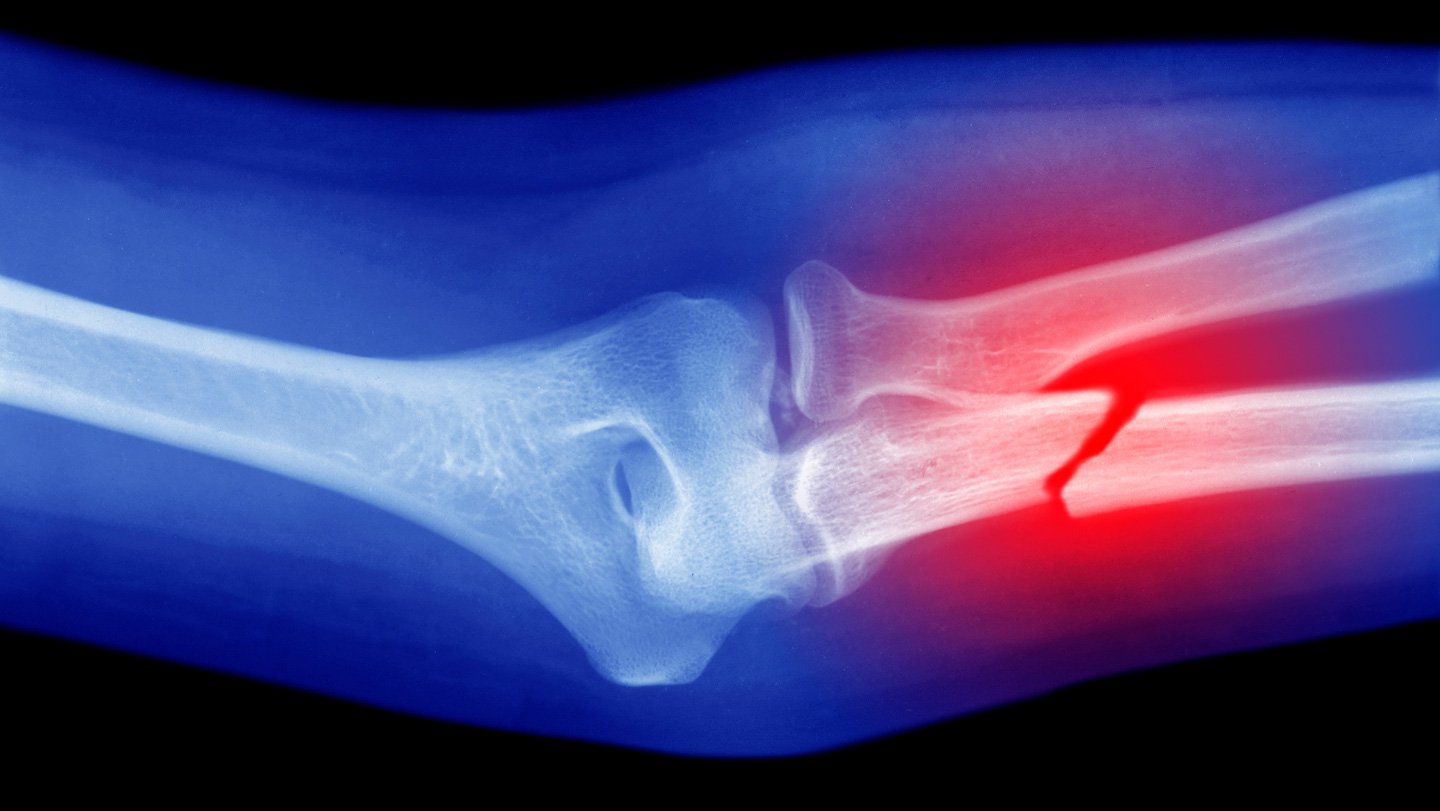

Lee and his colleagues tested the glue gun and bioink on femoral bone fractures in rabbits. Comparing results from rabbits receiving the therapy with a control group receiving regular bone cement, the team found that the former group had better healing and regeneration of bone tissue. The animals also showed no signs of infection during the 12 weeks following surgery.